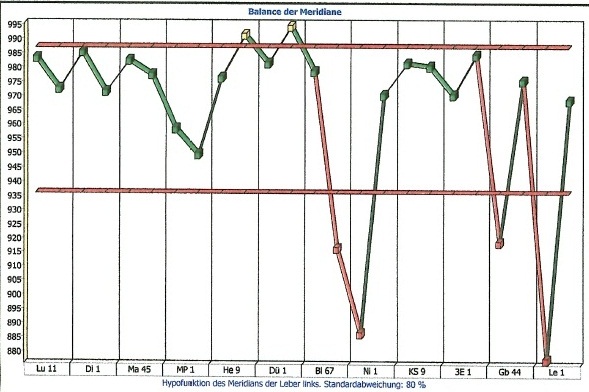

Nachfolgend Ergebnisse einer Studie, die über die Messung des menschlichen Meridiansystems aus der Traditionellen Chinesischen Medizin durchgeführt wurde, vor und nach der Betrachtung von Elementarkunst.

Sie können unter Fakten, Ergebnisse aus meiner Studie über die Wirkung der Initiativbilder einsehen, unter "Indirekt" Person 1 und 2 vorher und nachher.